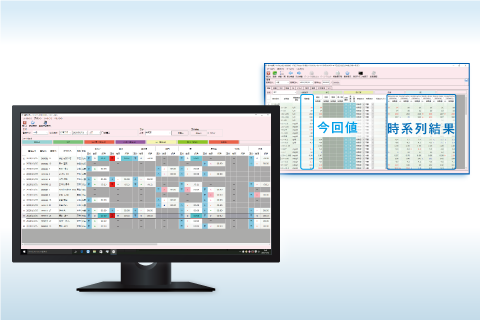

レポートシステム 検査システム

検査システム 健診システム